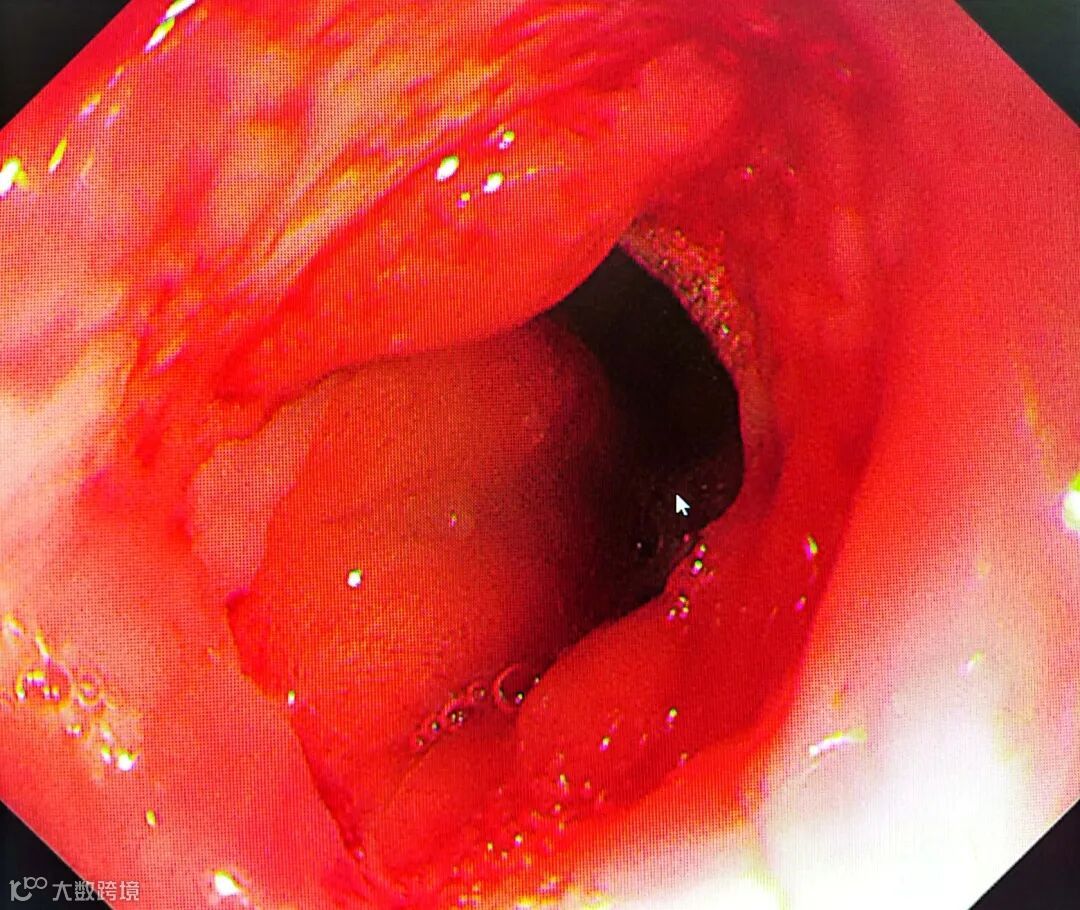

通过手术

王奶奶的食管吻合口

由0.4厘米扩张到了1.4厘米

术后病情平稳

身体也没不适症状

在慢慢地恢复中